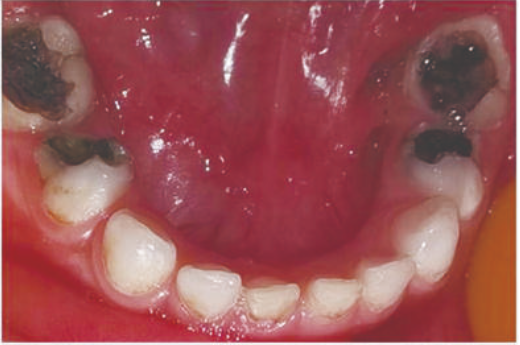

乳磨牙缺损较大

预成冠修复后